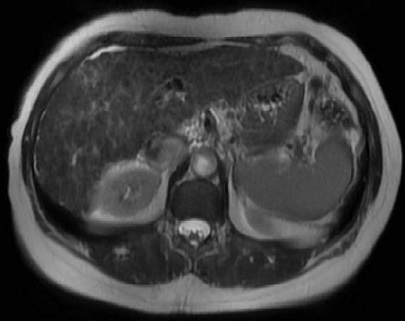

Image radiologique IRM du

foie en T2 coupe axiale : Foie a petite taille a

bord irregulier avec hypertension portal ,

splenomegalie et ascite important |

|

Image en coupe coronale |

Aspect hyposignal de

parenchyme du foie par la deposite de fer dans

l'hemochomatose du foie . Image radiologique IRM

ponderation T1 , en coupe axiale |

Dans la ponderation T2 IRM , la

parenchyme du foie est le plus hyposignal que les

muscles paraspinales . Coupe IRM axiale a travers du

foie a ponderer sur T2 d'une hemochromatose du foie |